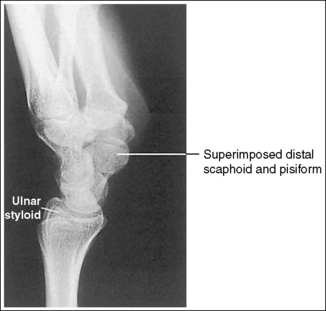

See Figure 4-36 and Box 4-13.

Contrast and density are adequate to demonstrate the pronator fat stripe and surrounding posterior wrist soft tissue.

• The pronator fat stripe is one of the soft tissue structures that should be demonstrated on all lateral wrist projections (Figure 4-37). It is located parallel to the anterior (volar) surface of the distal radius, is normally convex, and lies within 0.25 inch (0.6 cm) of the radial cortex. Bowing or obliteration of this fat stripe may be the only indication of a subtle radial fracture.

The wrist is in a lateral projection. The anterior aspect of the distal scaphoid and pisiform are aligned, and the radius and ulna are superimposed.

• A lateral projection of the wrist is accomplished by flexing the elbow 90 degrees and abducting the humerus until it is parallel with the IR, placing the entire arm on the same horizontal plane. Rotate the wrist into a lateral projection with its ulnar (medial) aspect against the IR (Figure 4-38). To ensure a true lateral projection, place the palmar aspect of your thumb and forefinger against the anterior and posterior aspects, respectively, of the patient's wrist joint, as shown in Figure 4-39. Adjust wrist rotation until your thumb and finger are aligned perpendicular to the IR.

• Detecting wrist rotation. The relationship between the pisiform and distal aspect of the scaphoid can best be used to discern whether a lateral wrist projection has been obtained. On a lateral projection, these two carpals should be superimposed, with their anterior aspects aligned. When the wrist is rotated, the anteroposterior relationship between the distal scaphoid and pisiform changes, and the pronator fat stripe is obscured. If the anterior aspect of the distal scaphoid is positioned posterior to the anterior aspect of the pisiform, the patient's wrist was externally rotated (see Image 45). If the anterior aspect of the distal scaphoid is positioned anterior to the anterior aspect of the pisiform, the patient's wrist was internally rotated (see Images 46 and 47). A second method of determining how to reposition a rotated lateral wrist projection uses the radius and ulna. The ulna is positioned anterior to the radius when the wrist was externally rotated and the ulna is positioned posterior to the radius when the wrist was internally rotated. Because the exact amount of superimposition of the radius and ulna depends on the position of the humerus, and their poor positioning is not as sensitive, you should always view the pisiform and distal scaphoid relationship when determining whether the wrist is in a lateral projection.